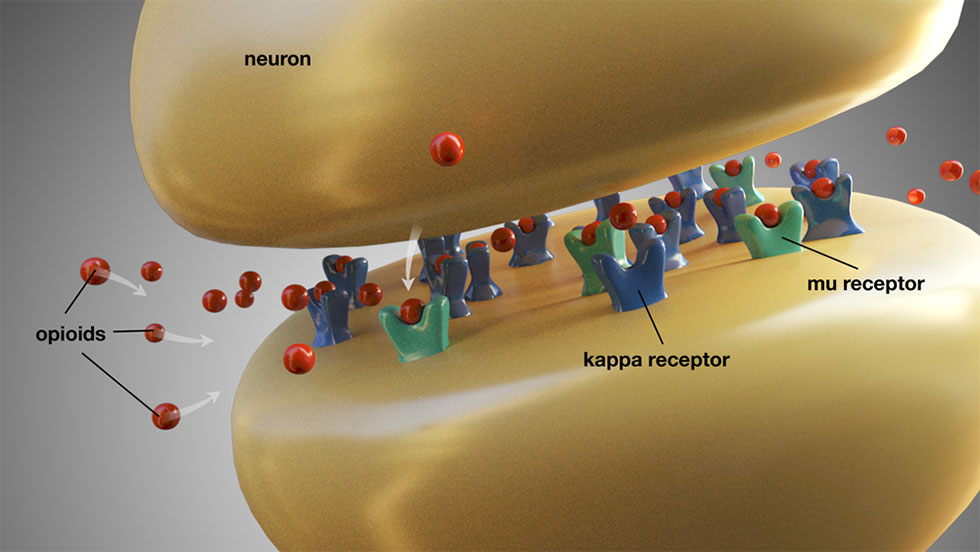

Τα οπιοειδή που συνταγογραφούνται συνήθως για τον οδοντικό πόνο περιλαμβάνουν την κωδεΐνη, την υδροκωδόνη, την οξυκωδόνη και την τραμαδόλη. Αυτά τα φάρμακα μπορούν να συνταγογραφηθούν από μόνα τους ή σε συνδυασμό με ακεταμινοφαίνη. Τα οπιοειδή ασκούν τη δράση τους αλληλεπιδρώντας με τους μ- και κ-υποδοχείς στο κεντρικό νευρικό σύστημα και αλλοιώνουν την αντίληψη του πόνου (Εικ. 5). Μπορούν να δημιουργήσουν μία αίσθηση ευφορίας και να μειώσουν το άγχος. Έτσι, ακόμη και εάν είναι πιθανόν να μην προσφέρουν πλήρη ανακούφιση από τον πόνο, ενδεχομένως να κάνουν τους ασθενείς να ασχολούνται λιγότερο με τον πόνο που νιώθουν. Τα οπιοειδή συνοδεύονται από μία πληθώρα παρενεργειών, στις οποίες συμπεριλαμβάνονται η ναυτία, ο έμετος, η δυσκοιλιότητα, τα ψυχοκινητικά προβλήματα και η καταστολή του ΚΝΣ.